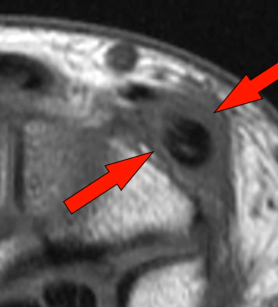

Syndrome de l’Intersection Distale

- Croisement des 2e et 3e compartiment (Extenseurs du Carpe Vs Long Extenseur du Pouce)

- Se fait 4cm plus bas que le tubercule de Lister (bien couvrir sur IRM !)

- Oedème Péritendineux (pas dans la gaine)